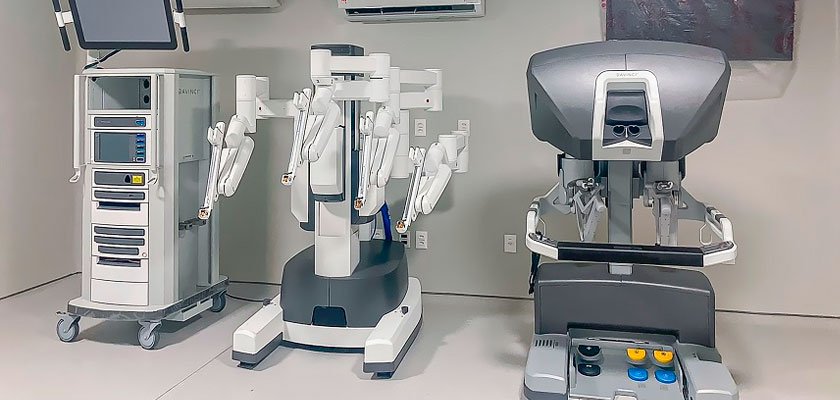

Cirurgia Robótica

A cirurgia robótica é a mais moderna técnica cirúrgica utilizada em procedimentos urológicos, oferecendo alta precisão e menos invasividade. Com o auxílio do sistema robótico, o cirurgião tem visão ampliada em 3D e movimentos mais delicados, proporcionando resultados superiores.

Benefícios:

- Menor sangramento e menor risco de complicações

- Precisão milimétrica nos movimentos cirúrgicos

- Menos dor no pós-operatório

- Recuperação mais rápida e alta hospitalar precoce

- Menor impacto na função urinária e sexual